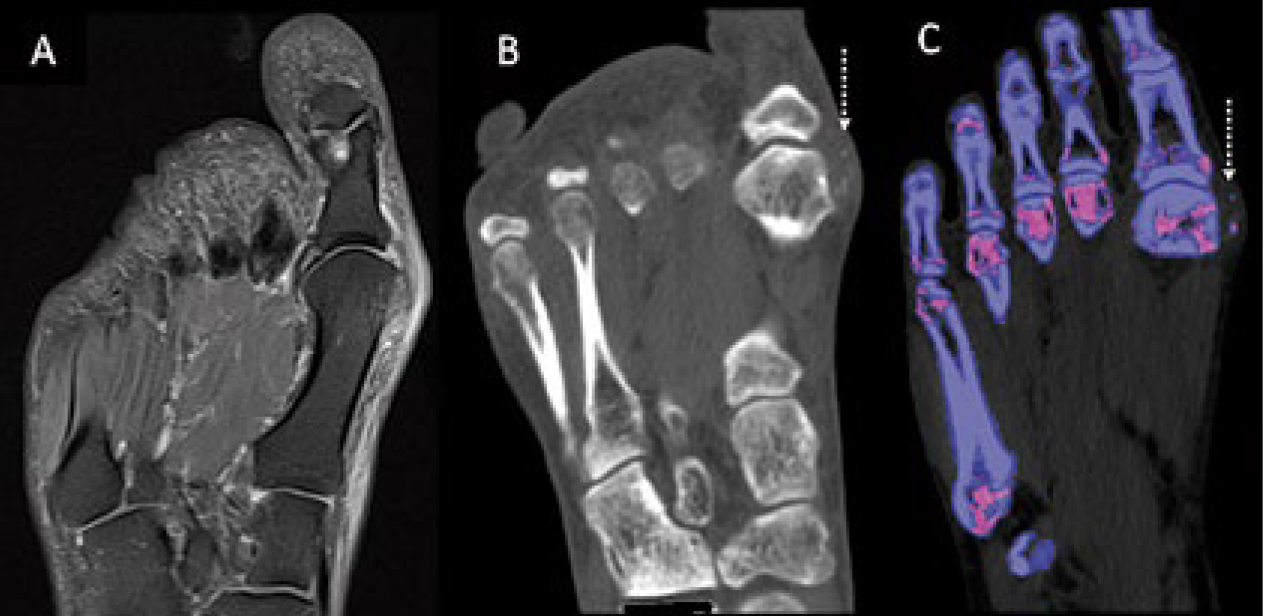

Descubra a inovação que permite à Ressonância Magnética detalhar o osso com precisão de Tomografia Computadorizada.

Veja como a ressonância magnética é usada para diagnosticar e acompanhar lesões esportivas com alta precisão.